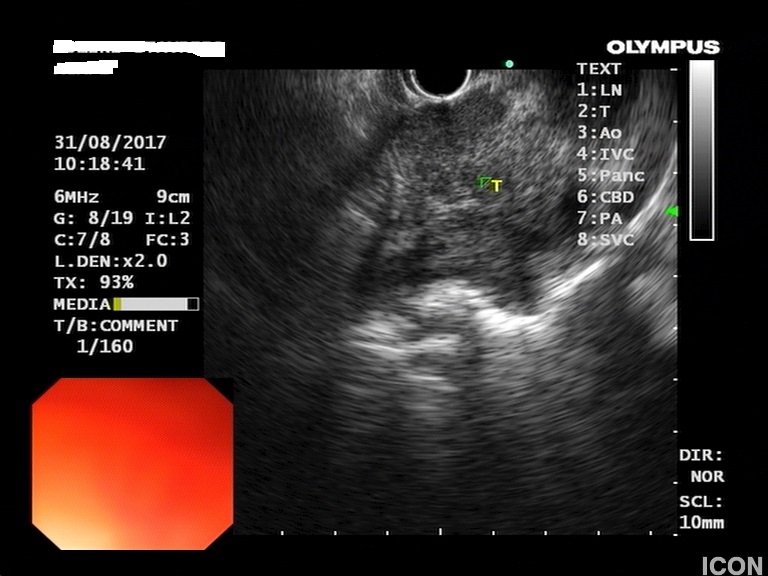

Ο ασθενής υποβλήθηκε σε ενδοσκοπικό υπέρηχο που έδειξε μια υποηχοϊκή μάζα διαμέτρου 21 χιλιοστών, με σαφή όρια, στην παγκρεατική κεφαλή και μεγάλη διάταση του χοληδόχου πόρου και του παγκρεατικού πόρου (διάμετρος 12 χιλιοστά).

Η μάζα είχε ξεκάθαρο διαχωριστικό όριο λίπους από την άνω μεσεντέριο φλέβα και δεν διηθούσε κανένα άλλο μεγάλο αγγείο της περιοχής (πυλαία φλέβα, σπληνοπυλαία συμβολή και αρτηρίες). Έγινε βιοψία με λεπτή βελόνη (FNA Χ3) και το κυτταρολογικό υλικό ήταν θετικό για αδενοκαρκίνωμα παγκρέατος. Το νεόπλασμα κρίθηκε χειρουργήσιμο και ο ασθενής υποβλήθηκε σε επέμβαση Whipple κατά την οποία αφαιρέθηκε πλήρως η παγκρεατική κεφαλή και ο όγκος σε υγιή όρια αλλά και 12 λεμφαδένες που ήταν όλοι αρνητικοί για κακοήθεια. Ο ασθενής υποβάλλεται σε συμπληρωματική χημειοθεραπεία.

Μάζα σώματος παγκρέατος στον ενδοσκοπικό υπέρηχο

Διαχωριστικό όριο μεταξύ μάζας και αγγείου

Λήψη βιοψίας (FNA)